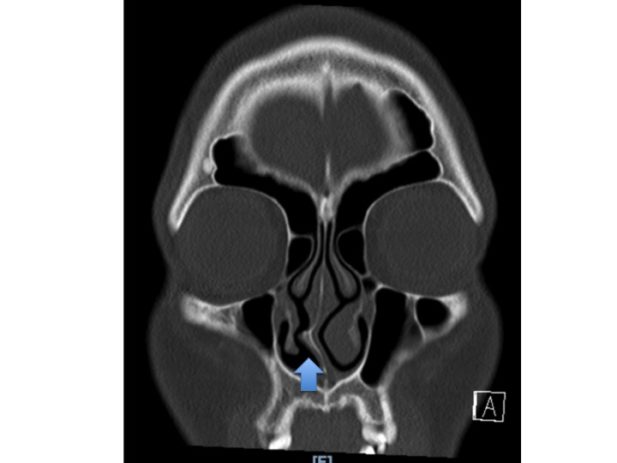

- Imaging tests: CT scans may be used if more detailed anatomical information is required, especially before surgery.